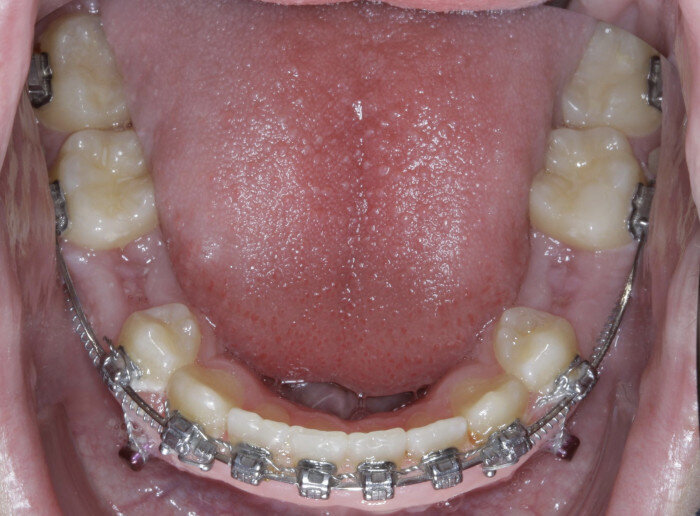

TADs are placed at the second visit with a 14 × 25 mm copper (Cu) and nickel–titanium (NiTi) wire and are tied from the anchor to the wire with an elastic thread (surgical thread; Fig. 6). Once the patient has progressed to larger Cu–NiTi wires and stainless steel, the TADs are tied to the wire using a power chain looped to the wire, or NiTi closing springs, depending on the thickness of the tissue (Figs. 7 & 8).

Once the intrusion has been completed, the TADs are tied to the wire and vertical elastics are used to close the bite without relapse of the intrusion. If buccal crown tip is seen, owing to the movement created by the intrusion, a power chain torquing sling is used to encourage lingual crown tipping and to prevent flaring of the incisors (Fig. 9). Once the case has been completed, the appliance is removed and a gingivectomy is performed to idealise the tissue shape and the final contours are made to the hard tissue (Figs. 10–12, end of treatment).